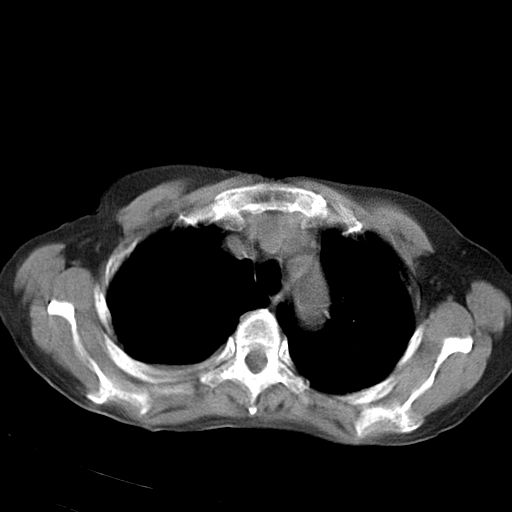

以下是引用jiazh在2006-12-7 20:37:00的发言:[br]肝脏周围半狐形低密度影,肝脏表面受压推移,考虑膈下脓肿可能性大;2、右侧胸腔积液

以下是引用拾荒者在2006-12-7 21:44:00的发言:[br]肝内外胆管多发结石,右膈下多发脓肿,右胸膜腔及叶间裂积液,左肾囊肿。[br] [br]